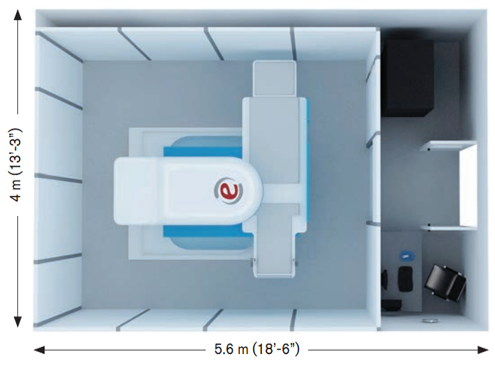

Economical Siting and OperationItalian

This Turnkey package offers dedicated MSK MRI with weight bearing capabilities to your practice, Light-weight pavilion style RF shielding can be installed without complex construction or costly renovations to your facility.